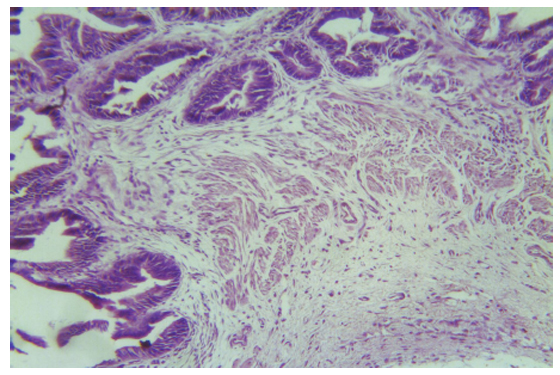

Միջանկյալ շրջանում (3-րդ ամիս) մանրադիտակային հետազոտության ժամանակ վիրահատական դաշտի եզրերից դուրս լորձաթաղանթի ծալքավորումը պահպանված էր: Այն պաստառված էր գլանաձև էպիթելով: Վերջինիս ամբողջականությունն ու բևեռացումը նույնպես պահպանված էին: Էպիթելի տակ հստակ երևում էր փուխր շարակցական հյուսվածքով ներկայացված լորձաթաղանթի սեփական թիթեղը, որտեղ, ի տարբերություն վաղ շրջանի, այլևս այտուց չէր հայտնաբերվում: Սակայն շուրջանոթային տարածություններում հայտնաբերվում էին հատուկենտ բջջային կուտակումներ` ներկայացված նեյտրոֆիլներով, էոզինոֆիլներով և պլազմատիկ բջիջներով:

Մկանային շերտում այտուց, արյան շրջանառության խանգարումներ` կանգ, արյունազեղում, թրոմբագոյացում չեն հայտնաբերվել (նկ. 1): Սակայն Վան-Գիզոնի մեթոդով ներկված հյուսվածաբանական հատածներում հայտնաբերվում էին առանձին մկանաթելեր` սնուցախանգարման նշաններով` բջջաթաղանթի վատ ուրվագծմամբ և քրոմատինային նյութի թերգունակավորմամբ: Այս հանգամանքը բացատրվում էր հետվիրահատական վաղ շրջանի արյան և ավշի շրջանառության խանգարումներով, որոնք էլ պատճառ էին հանդիսացել միոցիտների դեռևս չվերականգնված սնուցախանգարումների:

Լեղապարկի ադվենտիցիալ թաղանթը, որը ճագարների մոտ բավական լավ է արտահայտված, նույնպես զերծ էր արյան, ավշի շրջանառության և սնուցախանգարման նշաններից: Այդ մասին էին վկայում վերը նշված մեթոդներով հյուսվածաբանական հատածների ներկման արդյունքները:

Նկ. 1 Լորձաթաղանթի ծալքավորումը պահպանված է: Լորձաթաղանթի սեփական թիթեղում, ինչպես նաև մկանային և ադվենտիցիալ շերտերում այտուցը, շրջանառական խանգարումները բացակայում են:

Հեմատոքսիլին-էոզին, x 400